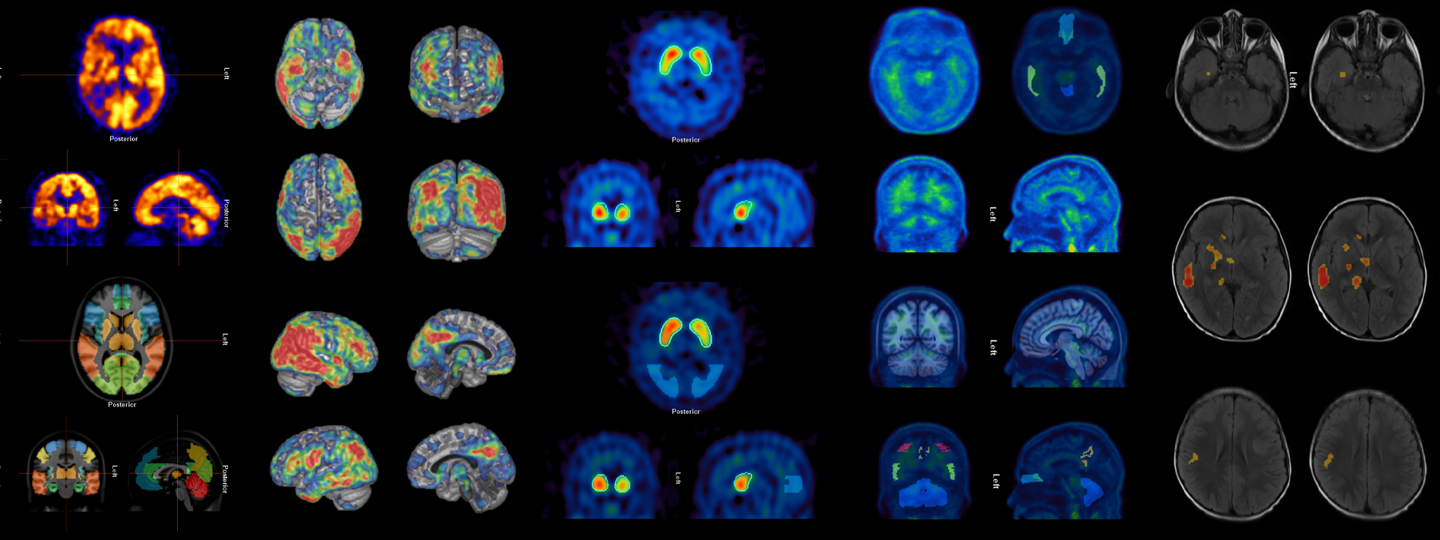

Quantification and visualization for a confident diagnosis

Hermia Neurology has a fully automated workflow for the reorientation of brain scans, quantification and localization of abnormal perfusion and receptor regions. It fits and compares patient images to three-dimensional reference templates created from images of normal studies.

Fast and accurate, the application provides physicians with all necessary quantification and visualization to support a confident diagnosis.

Fully automatic processing, visualization and quantification of brain scans

Data is processed, quantified, and displayed within seconds

Reference databases for all common SPECT and PET tracers

Personalized comparison with a normal population

Brain Region Atlas and Z-score Maps

Localization of abnormal regions and complete statistical analysis

3D Surface projection

Easy to interpret results for your referring neurologist or family physician

Automatic and accurate deformable registration

At the core of the application is an advanced registration algorithm that brings the patient's brain into alignment with the chosen normal template. The registration algorithm is a proven, fully automatic, deformable registration method utilizing a novel adaptive principle-component template to accurately align scans for quantitative analysis [1].

Reference databases for all common SPECT, and PET tracers

The neurology application from Hermes Medical Solutions features normal reference databases for all common tracers: 18F-FDG, 123I-FP-CIT (Datscan), PET amyloid, and cerebral perfusion SPECT (99mTc-ECD, 99mTc-HMPAO). This provides personalized comparisons with healthy controls.

Results can be reported for pre-defined anatomical regions, or as a z-score map showing you the exact localization of abnormal areas. Hermia Neurology provides both voxel-based and region-based analysis of brain scans utilizing an integrated brain atlas as well as 3D stereotactic surface projections.

Voxel-based analysis performs voxel-by-voxel comparison of the patient brain scan with a template of healthy controls. Areas of statistically significant difference from normal are visualized as color coded overlays.

Region-based analysis provides quantification of brain anatomical regions with statistics calculated on a region-by-region basis. The patient's regional statistics are compared to those from healthy controls and regional z-scores are presented in a table.

Easy to interpret 3D surface projection for referring neurologist

3D stereotactic surface projections allow for easy understanding of results for your referring neurologist or family physician, as well as facilitating patient communication. It is also possible to fuse an externally acquired patient MR scan with the functional deviation image for anatomical guidance.